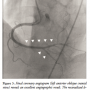

Diagnostic coronary angiography revealed a lesion with CTO in the middle segment of the RCA (Figure 1A). There was no significant stenosis in the left coronary artery. The distal segment of the RCA was supplied mainly by collateral vessels from a major septal branch originating from the left anterior descending artery (Figure 1B). Importantly, the exit of the CTO was a bifurcated site between the posterior atrioventricular (PAV) artery and posterior descending artery (PDA) (Figure 1B). We planned to perform PCI for the RCA CTO to improve the patient’s symptoms.

After obtaining informed consent, PCI of the CTO was performed. An 8 Fr AL1 guiding catheter with a side hole (Mach 1; Boston Scientific) was negotiated into the RCA and a 7 Fr VL3.5 guiding catheter with a side hole (Mach 1) was introduced into the left coronary artery. Because the exit of the CTO was bifurcated and the septal channel was well visualized at the time of diagnostic coronary angiography, we initially attempted a retrograde approach. A Fielder FC guidewire (Asahi Intecc) with a Corsair microcatheter (Asahi Intecc) was introduced into the targeted proximal major septal branch. The guidewire was then removed, and selective tip injection through the Corsair was performed to clarify the connection between the septal branch and the PDA (Figure 2A). The channel was well visualized angiographically, and a Sion guidewire (Asahi Intecc) with a Corsair was successfully introduced into the septal channel. After introducing the guidewire into the distal RCA from PDA to PAV, the Corsair was advanced into the PDA. Tip injection through the Corsair from the PDA was performed, which confirmed that the exit of the CTO was at the point of bifurcation between the PAV and PDA (Figure 2B). The guidewire was then exchanged for a Gaia Second (Asahi Intecc) and advanced retrograde into the CTO from the PDA. Because the retrograde wire was not advanced into the proximal true lumen, reverse controlled antegrade and retrograde subintimal tracking (CART) technique was performed with a 2.5 x 15 mm Sapphire balloon (Orbusneich Medical) (Figure 2C). Finally, a Conquest Pro guidewire (Asahi Intecc) was successfully introduced into the proximal true lumen. The retrograde wire was advanced into the antegrade guiding catheter with the Corsair and exchanged for a 330 cm RG3 guidewire (Asahi Intecc). Wire externalization was then completely achieved.

advanced into the bifurcation lesion antegrade, and a 1.75 x 15 mm Sapphire balloon (Orbusneich Medical) was advanced retrograde. The bidirectional kissing-balloon technique was then performed (Figure 2F). Following this, we successfully navigated a Balance guidewire (Abbott Vascular) antegrade into the PAV with a Crusade. Subsequently, we performed antegrade kissing-balloon angioplasty with a 2.0 x 15 mm Sapphire balloon in the PDA and a 1.75 x 15 mm Sapphire balloon in the PAV (Figure 2G). A 2.25 x 23 mm Xience Prime stent was deployed from the middle segment of the RCA to the PAV (Figure 2H). Postdilatation was performed with stent balloons, and a final coronary angiogram revealed an excellent result, with preserved flow in both the PAV and PDA (Figure 3). The postprocedure course was uneventful, and no major complications, including severe ischemic events, heart failure, or access-site complications, were observed. The patient was discharged 2 days after the procedure without symptoms.